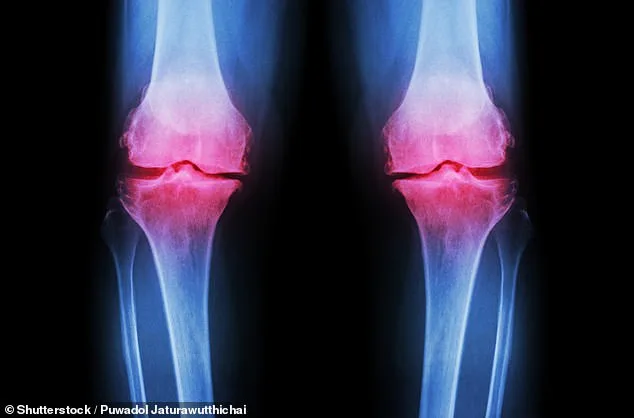

Moreover, the bones begin to weaken during this time, putting individuals at greater risk of fractures later in life. The Royal Osteoporosis Society has highlighted that peak bone health is reached by the age of 30. However, bone density declines with time. If action is not taken in the 40s, individuals may develop osteopenia, the early stage of bone thinning that can lead to osteoporosis. Research shows that up to 40 percent of over-50s may suffer from this condition. This is a growing public health crisis, with experts from the Academic Centre for Healthy Ageing at Queen Mary University of London, Professor Hamish Simpson, warning that many individuals may not be aware they are suffering from bone thinning until they experience a fracture.

To prevent this, experts recommend adopting a healthy lifestyle. According to Dr. Richie Abel of the Bone Health Research Group at Imperial College London, eating well, reducing alcohol intake, and increasing physical activity can significantly reduce the risk of future fractures. He also emphasizes the importance of a calcium-rich diet, where possible, and taking vitamin D supplements. Professor Simpson adds that physical activity is the most effective intervention, especially for bone health. 'Any increase in activity is beneficial, but for bones in particular you want loading exercises - jumping or skipping - which create the small shocks that stimulate bone growth,' he explains.